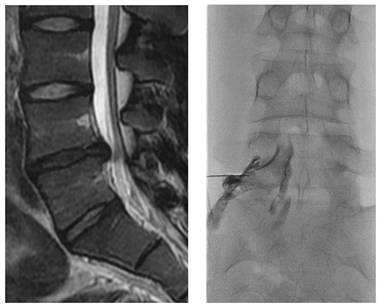

시술은 엎드린 자세 혹은 바로 누운 자세에서 시행합니다. 시술 부위를 완전히 소독한 이후에 실시간으로 영상을 확인하며 가는 바늘을 신경 주위 조직까지 삽입합니다. 이후 소량의 조영제를 주입하여 바늘이 경막외 공간에 위치한 것을 확인하고 국소마취제(부피바카인)와 스테로이드 약제를 주사합니다. 시술 시에는 신경이 자극되어 약간의 불편감이 있을 수 있으나 국소마취제가 통증을 완화합니다.

(좌)자기공명영상에서 진단된 요추 추간판 탈출증의 예

(우)영상장비 유도하 경막외 주사요법의 예